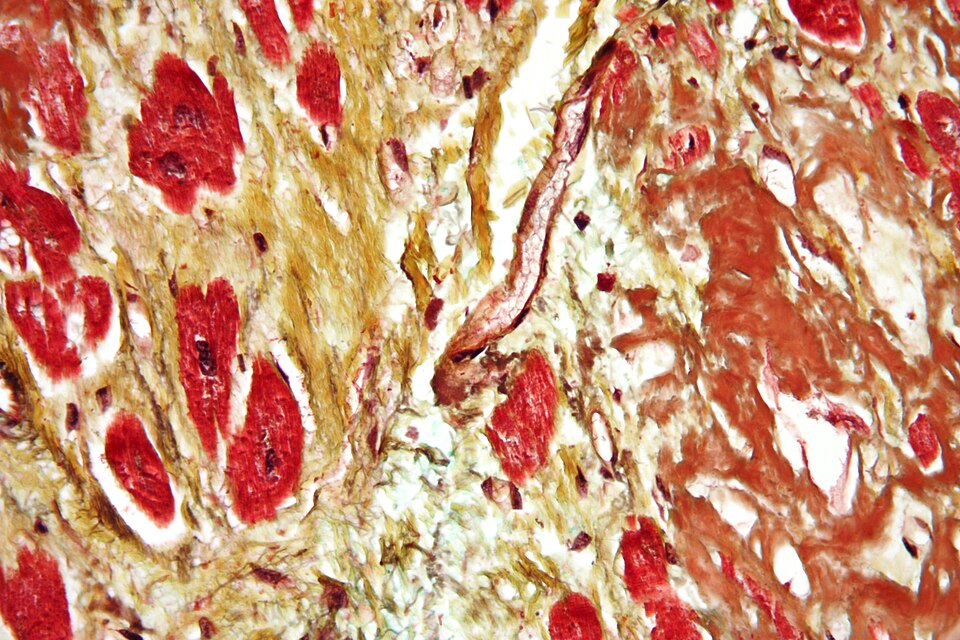

Heart Transplantation

The clash between life and death is starkest in heart transplantation, where the decision to replace a failing heart with a donor's is a battle against time and biology. Heart transplantation is not just a...